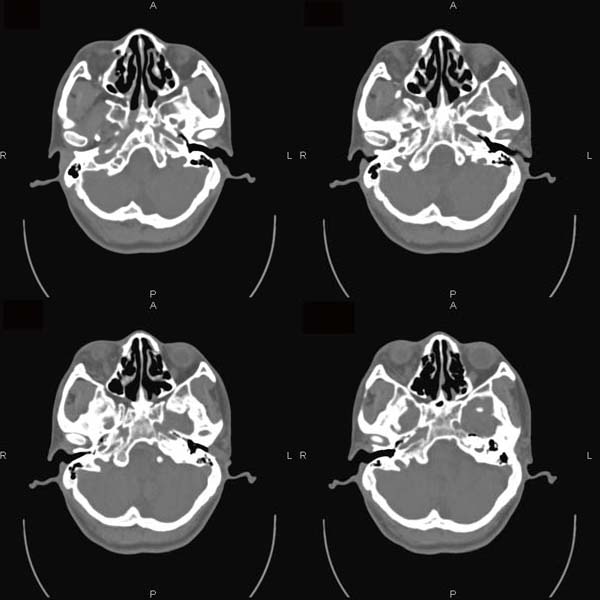

以下是引用逸风在2006-6-5 17:45:00的发言:[br]ct显示:右侧眼球轻度突出,眼环增厚,球后脂肪间隙模糊,可见点状高密度灶,同侧视神经稍增粗,周围眶壁骨质未见明显异常,眼环完整,球内未见明显异常密度.[br]诊断意见:1.右侧眼球钝挫伤合并球后间隙出血可能;2.右侧视神经挫伤待排.[br]建议必要时hrct扫描,排外其它.

以下是引用jiangjing在2006-6-5 23:41:00的发言:[br][图像处理较差]ct显示:右侧眼球轻度突出,眼环增厚,球后脂肪间隙模糊,可见点状高密度灶,同侧视神经稍增粗,周围眶壁骨质未见明显异常,眼环完整,球内未见明显异常密度.[br]诊断意见:1.右侧眼球钝挫伤合并球后间隙出血可能;2.右侧视神经挫伤待排.[br]建议必要时hrct扫描,排外其它